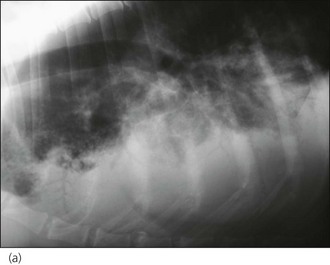

Plain thoracic radiographs (typically right lateral and dorsoventral (or left lateral) views) are useful in animals with regurgitation and may help to identify megaoesophagus, radiopaque oesophageal foreign bodies, aspiration pneumonia and mediastinal masses (Figures 22.1-22.3).

Figure 22.3 (a) Right lateral and (b) left lateral thoracic radiographs in a dog with severe aspiration pneumonia. Multiple air bronchograms are clearly visible in the ventral lung fields.

If megaoesophagus is considered a significant possibility, radiographs should be taken without sedation or general anaesthesia. Aspiration pneumonia is most commonly identified as an alveolar pattern with air bronchograms in the right middle lung lobe and ventral parts of the other lobes, especially cranioventrally (Figure 22.3). Radiographs must not be prioritized over oxygen therapy and cardiovascular stabilization in animals with severe dyspnoea at presentation and these animals should be subjected to minimum stress.